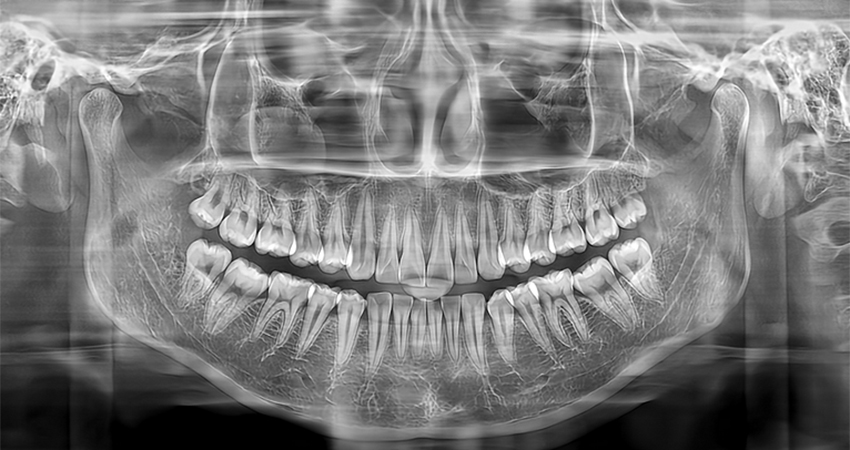

Панорамный аппарат Meyer обеспечивает стоматологов высококачественными панорамными и цефалометрическими снимками, который может быть использован для диагностики всего зубного ряда, нижней челюсти и ВНЧС. Он также подходит для оценки челюстно-лицевых переломов и разработки планов ортодонтического лечения.

Скриншоты снимков